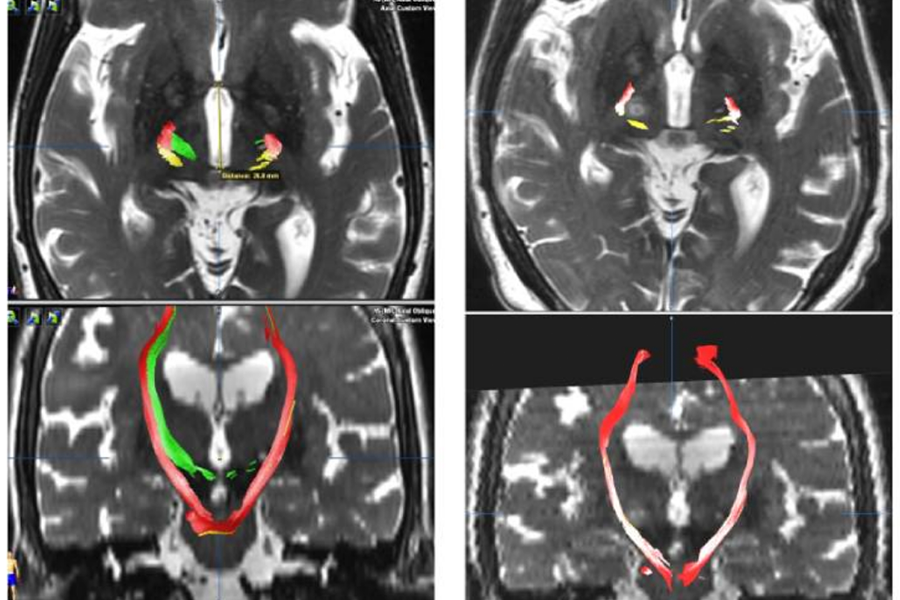

Axial and coronal images from (L) before bilateral treatment and (R) after the procedure. The green is the target of the MRgFUS ablation whereas the red and yellow portions are nearby structures. After treatment, the nearby structures remain untouched, showing that the brain was successfully ablated bilaterally without affecting nearby structures.